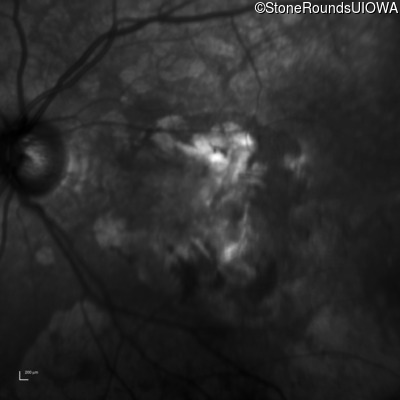

Infrared Fundus Photograph - Left - 20/160 -1

Exemplar